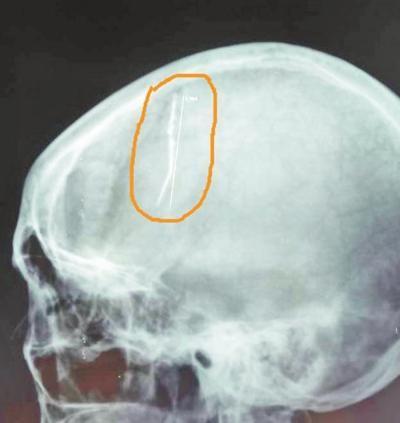

随后,王晓红被家人送往大医院检查。据医院神经外科副主任介绍,王晓红入院后,医生为其做了头颅X线检查。令人不可思议的是,检查结果显示,在她的脑部竟然有一根六七厘米长的钢针,从病人的右侧大脑顶部直插入左侧大脑深部。

在病因被确诊之后,医护人员抓紧制订治疗方案,希望可以尽快将异物安全取出。医生们决定为其实施开颅手术。在手术过程中,医生发现这根针已经生锈,被新生粘连的组织血管包裹住了,不能一下子拔出,且钢针已经深入对侧脑室内,如果贸然拔出可能会导致不可预料的大出血。

这无疑增大了手术的难度。在显微镜下,医生小心翼翼地将一根根新生血管及粘连的脑组织剥离,切开两侧大脑半球间的大脑镰,经过两个多小时的“雕刻式切除”,终于将藏于王女士大脑内的钢针完整地取出。目前,病人已顺利出院。